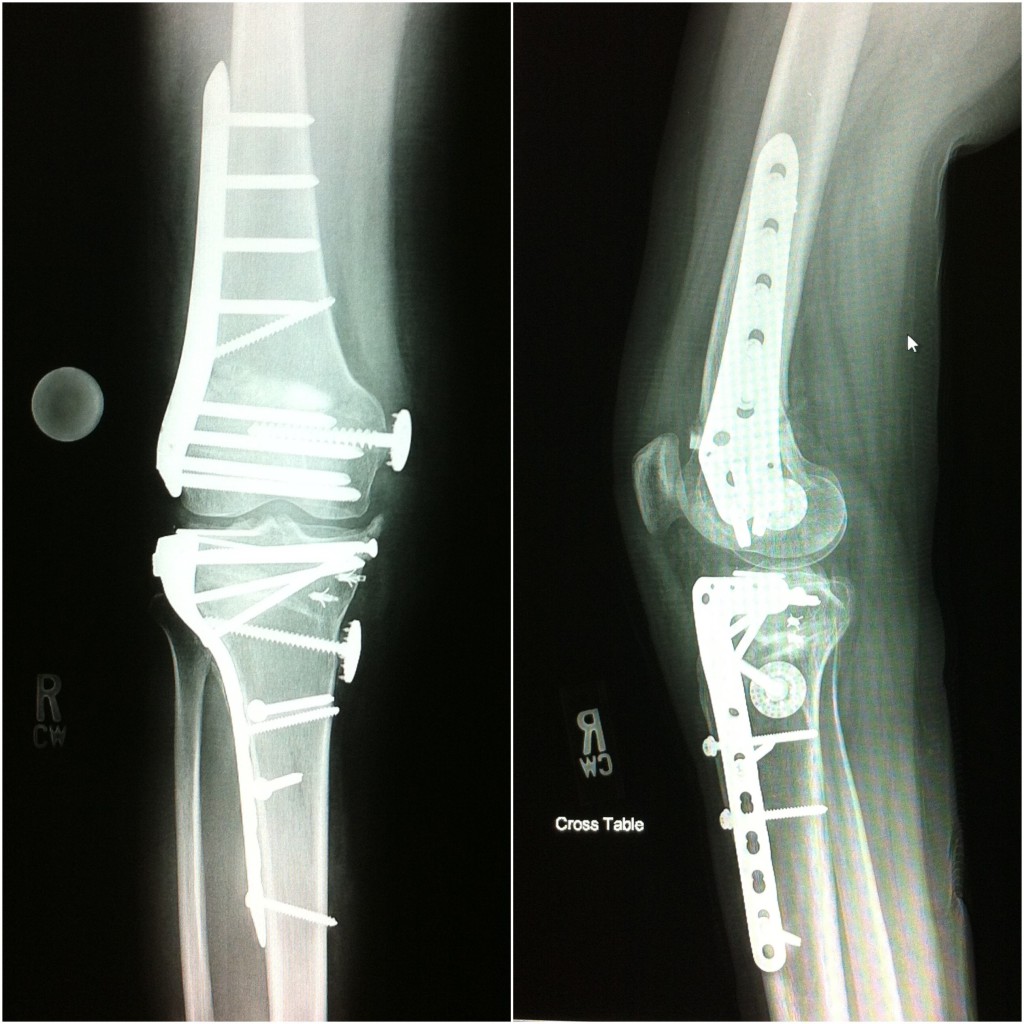

The events that transpired since my horrific ski accident left me feeling as though I would never walk again much less ski with my children. I had shattered both my tibia and fibula and 8 surgeries prior to visiting Dr. Fragomen's office. It has now been 9 months since my last surgery and I wanted to tell you about a magical time my family just had together. We are at Sunday River, a ski resort in Maine, I have donned my skis, and am skiing with my 11 year-old daughter, who wants to be a professional snow board rider when she grows up. This has been a very special weekend. This weekend also served as a trial run, as Cathy and I are getting married, slopeside, on December 28. All four of our children will be present. All this has been made possible by the hard work of you and all your colleagues at Hospital for Special Surgery. Without the dedication of your group, I am convinced prosthesis was in my future. It is with special gratitude that I write this letter, if there is ever anything I can do for your practice or for you personally, please feel free to contact me.